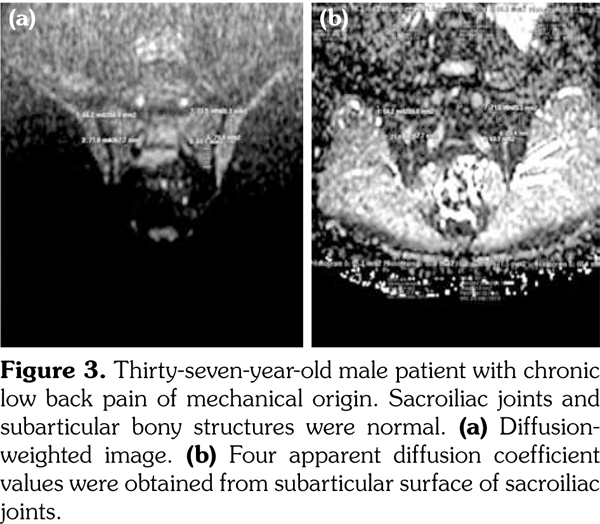

All patients underwent MRI at 1.5-Tesla superconducting eight channel MRI system (Achieva, Philips Medical Systems, Best, The Netherlands) provided with high-speed gradients. The following sequences of sacroiliac joints in the oblique coronal and axial planes as the standard protocol were obtained in the supine positions with a high-resolution phased-array coil: turbo spin-echo T1-weighted (repetition time/echo time, 600/minimum), turbo spin-echo T2-weighted (repetition time/echo time, 2100/80), T2-weighted spectral presaturation with inversion recovery (SPIR) (3100/70), T1-weighted SPIR (600/ minimum) with and without gadolinium-based contrast agents (0.1 mmoL/kg of body weight). All sequences contained lower lumbar spine (Figures 1a-c).

Diffusion-weighted imaging was performed by single-shot spin-echo echo-planar imaging technique with diffusion gradient b values of 0 and 600 s/mm2 (Figure 1d). The following DWI parameters were used: field of view: 25 (right-left) x 32 (anteroposterior) cm; number of excitations: 2; matrix size: 176x176; slice thickness: 4 mm; repetition time/echo time, 8000/minimum; intersection gap: none.

Sacroiliac joints were assessed according to ankylosing spondylitis criteria. Before evaluation of standard MRI protocol, patients’ information was removed from images. Afterwards, two experienced radiologists evaluated the images for the presence of inflammatory activity twice at separate sessions to assess interobserver variability. Following the examination of T2-weighted SPIR, contrast- enhanced T1-weighted SPIR, and DWIs at b values of 600 s/mm2, two radiologists and rheumatologists reached a consensus on the disease activity in the light of positive features of Berlin criteria. The DWIs were transferred to a separate workstation (Phillips, Extended MR workspace, 2.6.3.2.HF3, Netherlands). ADC maps were generated. T2-weighted SPIR images, contrast-enhanced images and diffusion-weighted images with ADC maps were put on the screen side by side. In the disease group, the hyperintense lesions on T2-weighted SPIR images and enhanced focuses on contrast- enhanced images were noted and the same lesions were marked on DWI images and ADC map. A circular ROI with a range of 40-75 mm2 was placed in those areas. In the control group a circular ROI was placed in the subarticular area of joints. Also, the same process was performed for the normal-appearing bone marrow areas near the joints of the disease group (Figure 2). Four standard measurements were conducted from each joint, including two on sacral and the other two on the iliac side for all patients (Figure 3). Additionally, two measurements were conducted from the fifth lumbar vertebra and one from each iliac wing (Figure 4). All measurements were performed twice. ADC values were expressed as square millimeters per second. The r-ADC ratio was calculated by dividing ADC value of subchondral bone or inflammatory lesions to ADC values of the fifth lumbar vertebra and iliac wings.